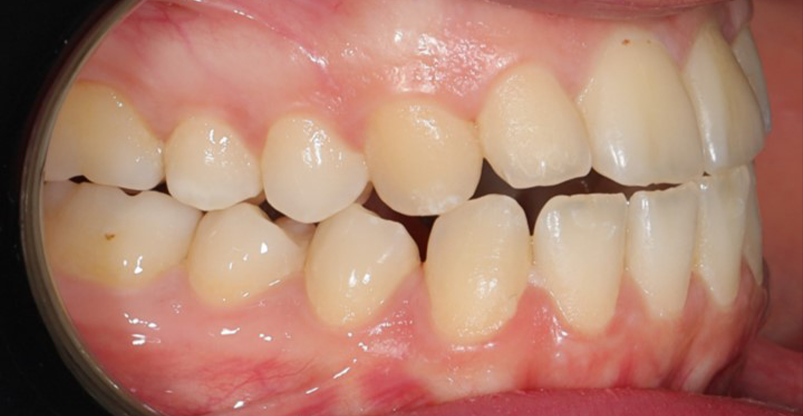

A 22-year-old female patient presented with a Class III malocclusion. She does not like her own profile. Her facial profile was straight with a slightly retrusive maxilla, the upper incisors were within normal inclination, and the lower incisors were retroclined. Bolton discrepency is on mandible for 6 teeth. A retruded upper lip and a normally positioned lower lip were noted. There was also a marked lack of midface support, and the constricted dental arches resulted in a narrow smile and pronounced dark buccal corridors.

Initial leveling in the maxillary arch was carried out with a 0.014 CuNiTi archwire. This was followed by a 0.018 CuNiTi wire, with stoppers positioned mesial to the molars and activated to provide protrusion of incisors. The mandibular arch was then bonded and initial alignment was achieved with a 0.014 CuNiTi wire, then both jaws are progressing to 0.014 × 0.0275 CuNiTi and subsequently 0.018 × 0.0275 CuNiTi for torque control.